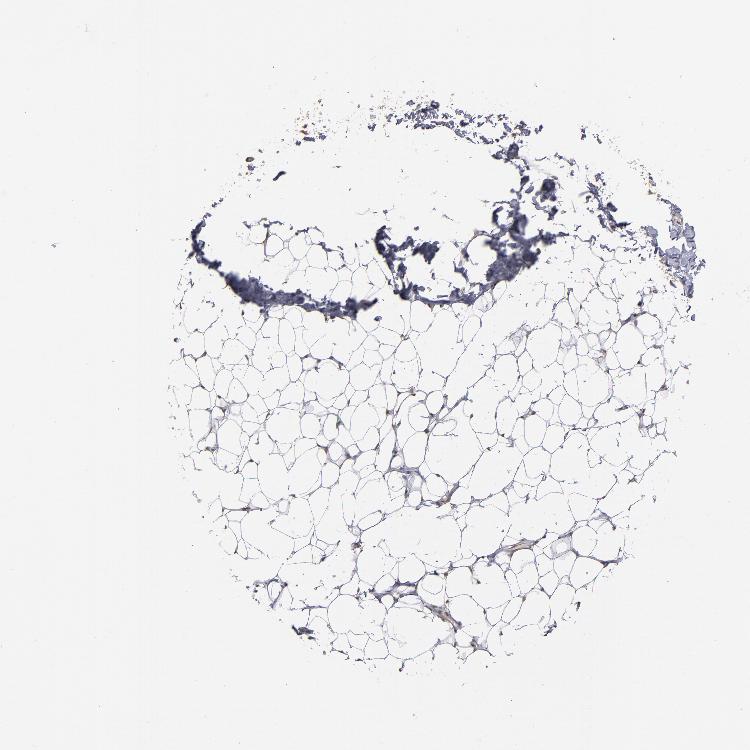

ADIPOSE TISSUE - Antibody stainingi

Antibody staining in the annotated cell types in the current human tissue is reported as not detected, low, medium, or high, based on conventional immunohistochemistry profiling in selected tissues. This score is based on the combination of the staining intensity and fraction of stained cells.

Each image is clickable and will lead to virtual microscopy that enables deeper exploration of all samples and also displays staining intensity scores, fraction scores and subcellular localization as well as patient and tissue information for each sample.

Antibody HPA002548Antibody CAB022718

Adipocytes Not detectedLow